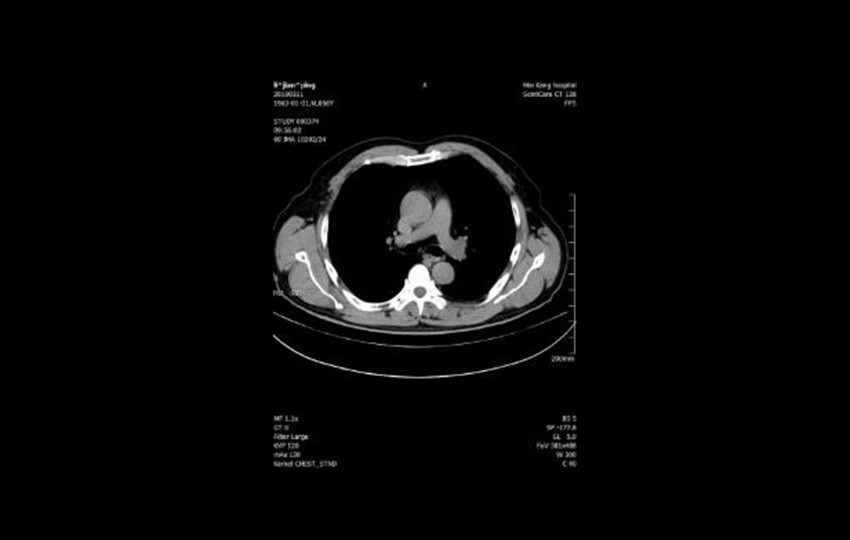

Caso 2-1<br>Mejor exploración del Tórax

Mejor exploración del Tórax